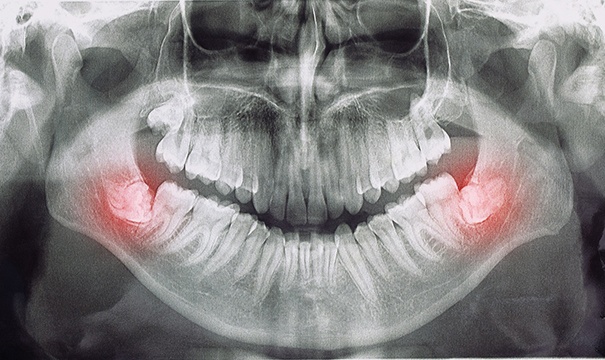

Actually, no! In fact, one article published in the Dental Research Journal estimated that up to 37% of the population is missing at least one of their wisdom teeth. That’s why it’s so important for your dentist in Newton to take X-rays annually and complete a comprehensive oral exam every six months. This ensures that they can monitor the development of the third set of molars and, if needed, perform an extraction.

Because the wisdom teeth erupt later than the other teeth, there often isn’t enough room for them in the mouth. Consequently, they may become trapped beneath the gums, which can result in significant pain and swelling. Furthermore, because the wisdom teeth often come in at an angle, they may push against the other teeth, potentially damaging them or pushing them out of alignment. Finally, the location of the wisdom teeth can make them difficult to clean properly, increasing your risk for cavities and other oral health issues.

Wisdom teeth that have emerged from beneath the gums can sometimes be removed via a simple extraction. This involves using a dental elevator to loosen the teeth until they can be gently taken out of their sockets. However, if your wisdom teeth are trapped under your gums, a surgical approach may be required. An incision will need to be made in the gums so that the teeth can be accessed. Furthermore, it might be necessary to divide the teeth into sections that can be removed one at a time.